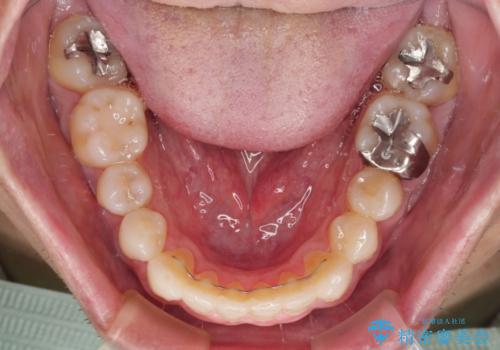

内側に転位した歯とボロボロのむし歯 インビザラインによる矯正治療とむし歯治療

ボロボロとなっていた歯は抜歯が必要な状態でしたが、舌側転位している歯を移動させることで抜歯スペースを埋めることができるため、矯正治療により歯列を整えることとしました。

矯正治療後には抜歯が必要な歯に隣接してむし歯となっていた歯をオールセラミッククラウンにて補綴治療を行うこととしました。

矯正治療開始時に、インビザライン矯正の加速装置を購入されましたが、インビザライン自体をあまりしっかりと使用できず、4年間の治療期間となりました。